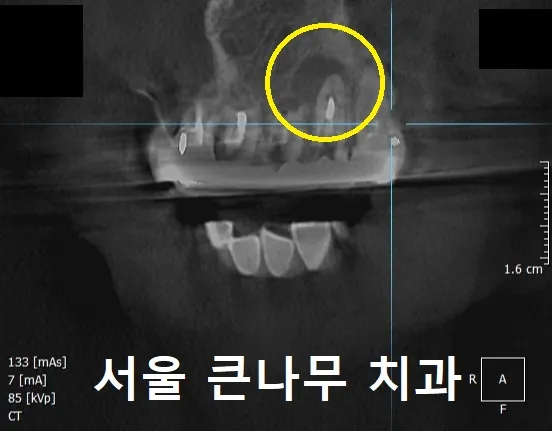

환자분께서는 단순한 잇몸 염증이라고 생각하셨지만, CBCT를 찍어 자세히 살펴보니, 뿌리끝 염증이 발견되었습니다.

한눈에 봐도 상당한 크기였는데요.

X-ray 사진을 통해 전과 후를 비교해 보았습니다.

치료전 염증 상태(왼), 치근단절제술 후 뼈이식된 모습(오)

왼쪽 사진이 치료전 고름 주머니가 차있는 상태이고, X-ray 상에서 까맣게 보이는 상태입니다.